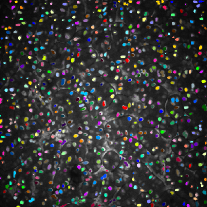

To make this clear, segmentation results were color coded using 3D connected component labeling and overlaid on the original volumes. The method from [20] cannot distinguish between nuclei and non-nuclei structures including noise. This is especially recognizable from segmentation results of Data-I in which multiple nuclei and non-nuclei structures are colored with the same color. As can be observed from Figure 6 and 6, segmentation masks are smaller than nuclei size and suffered from location shifts. Conversely, our proposed method shown in Figure 6 and 6 segments nuclei with the right shape at the correct locations.

Additionally, two synthetic data generation methods between CycleGAN and SpCycleGAN from the same synthetic binary image are compared in Figure 4. Here, the synthetic binary image is overlaid on the synthetic microscopy image and labeled in red. It is observed that our spatial constraint loss reduces the location shift of nuclei between a synthetic microscopy image and its synthetic binary image. Our realistic synthetic microscopy volumes from SpCycleGAN can be used to train our modified 3D U-Net.